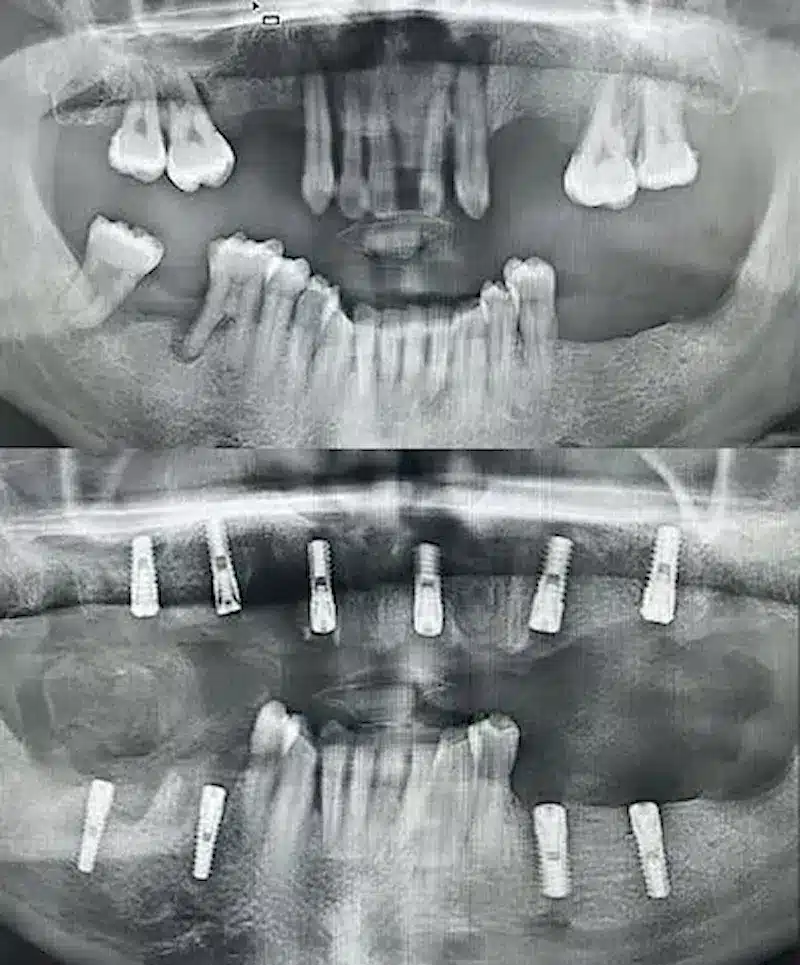

Dr. Seden Aksu is a specialist in modern implantology and surgical dentistry with extensive experience in the management of complex clinical cases. In her practice, she applies comprehensive surgical planning, minimally invasive techniques, and advanced regenerative technologies aimed at restoring both the function of the dentoalveolar system and the aesthetics of the smile. Dr. Aksu has significant experience in performing implant procedures, bone augmentation, and periodontal surgery, including the treatment of patients with severe bone loss. The primary goal of her work is to achieve stable, long-term outcomes in implant rehabilitation and the restoration of oral tissue health.